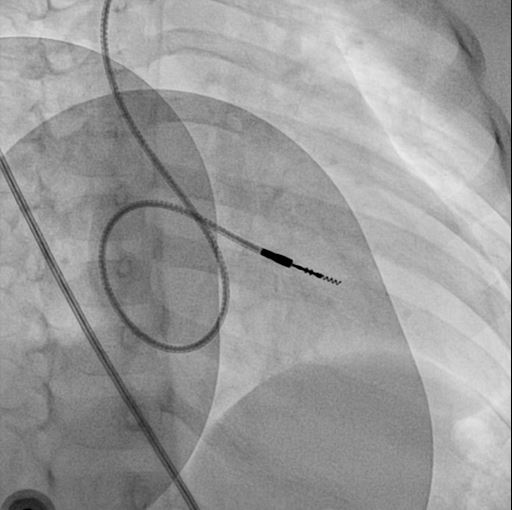

RVOT pacing

• Active fixation lead

• Stylet shaping

rvot_before_screw.jpg

rvot_lead.jpg